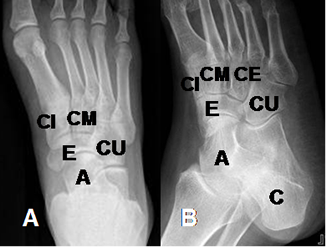

Estructuras óseas a tener en cuenta: Maléolo interno y maléolo externo, huesos del retropie (Calcáneo y talo o astrágalo), huesos del mediopie (Escafoides, cuboides, cuneiformes medial, medio y lateral) y huesos del antepie (Metatarsianos y falanges).

Las articulación tarsometatarsiana (Entre las cuñas/cuboides y los metatarsianos) es conocida como de Lisfranc y la mediocarpiana (Entre el calcáneo/talo y escafoides/cuboides), como de Chopart. (Fig 5).

Fig 4 B. Pie normal.

A: Rx AP y B: Rx Oblicua. C: Calcáneo. A: Astrágalo o talo. E: Escafoides.

CU: Cuboides. CI: Cuña interna. CM: Cuña media y CE: Cuña externa.